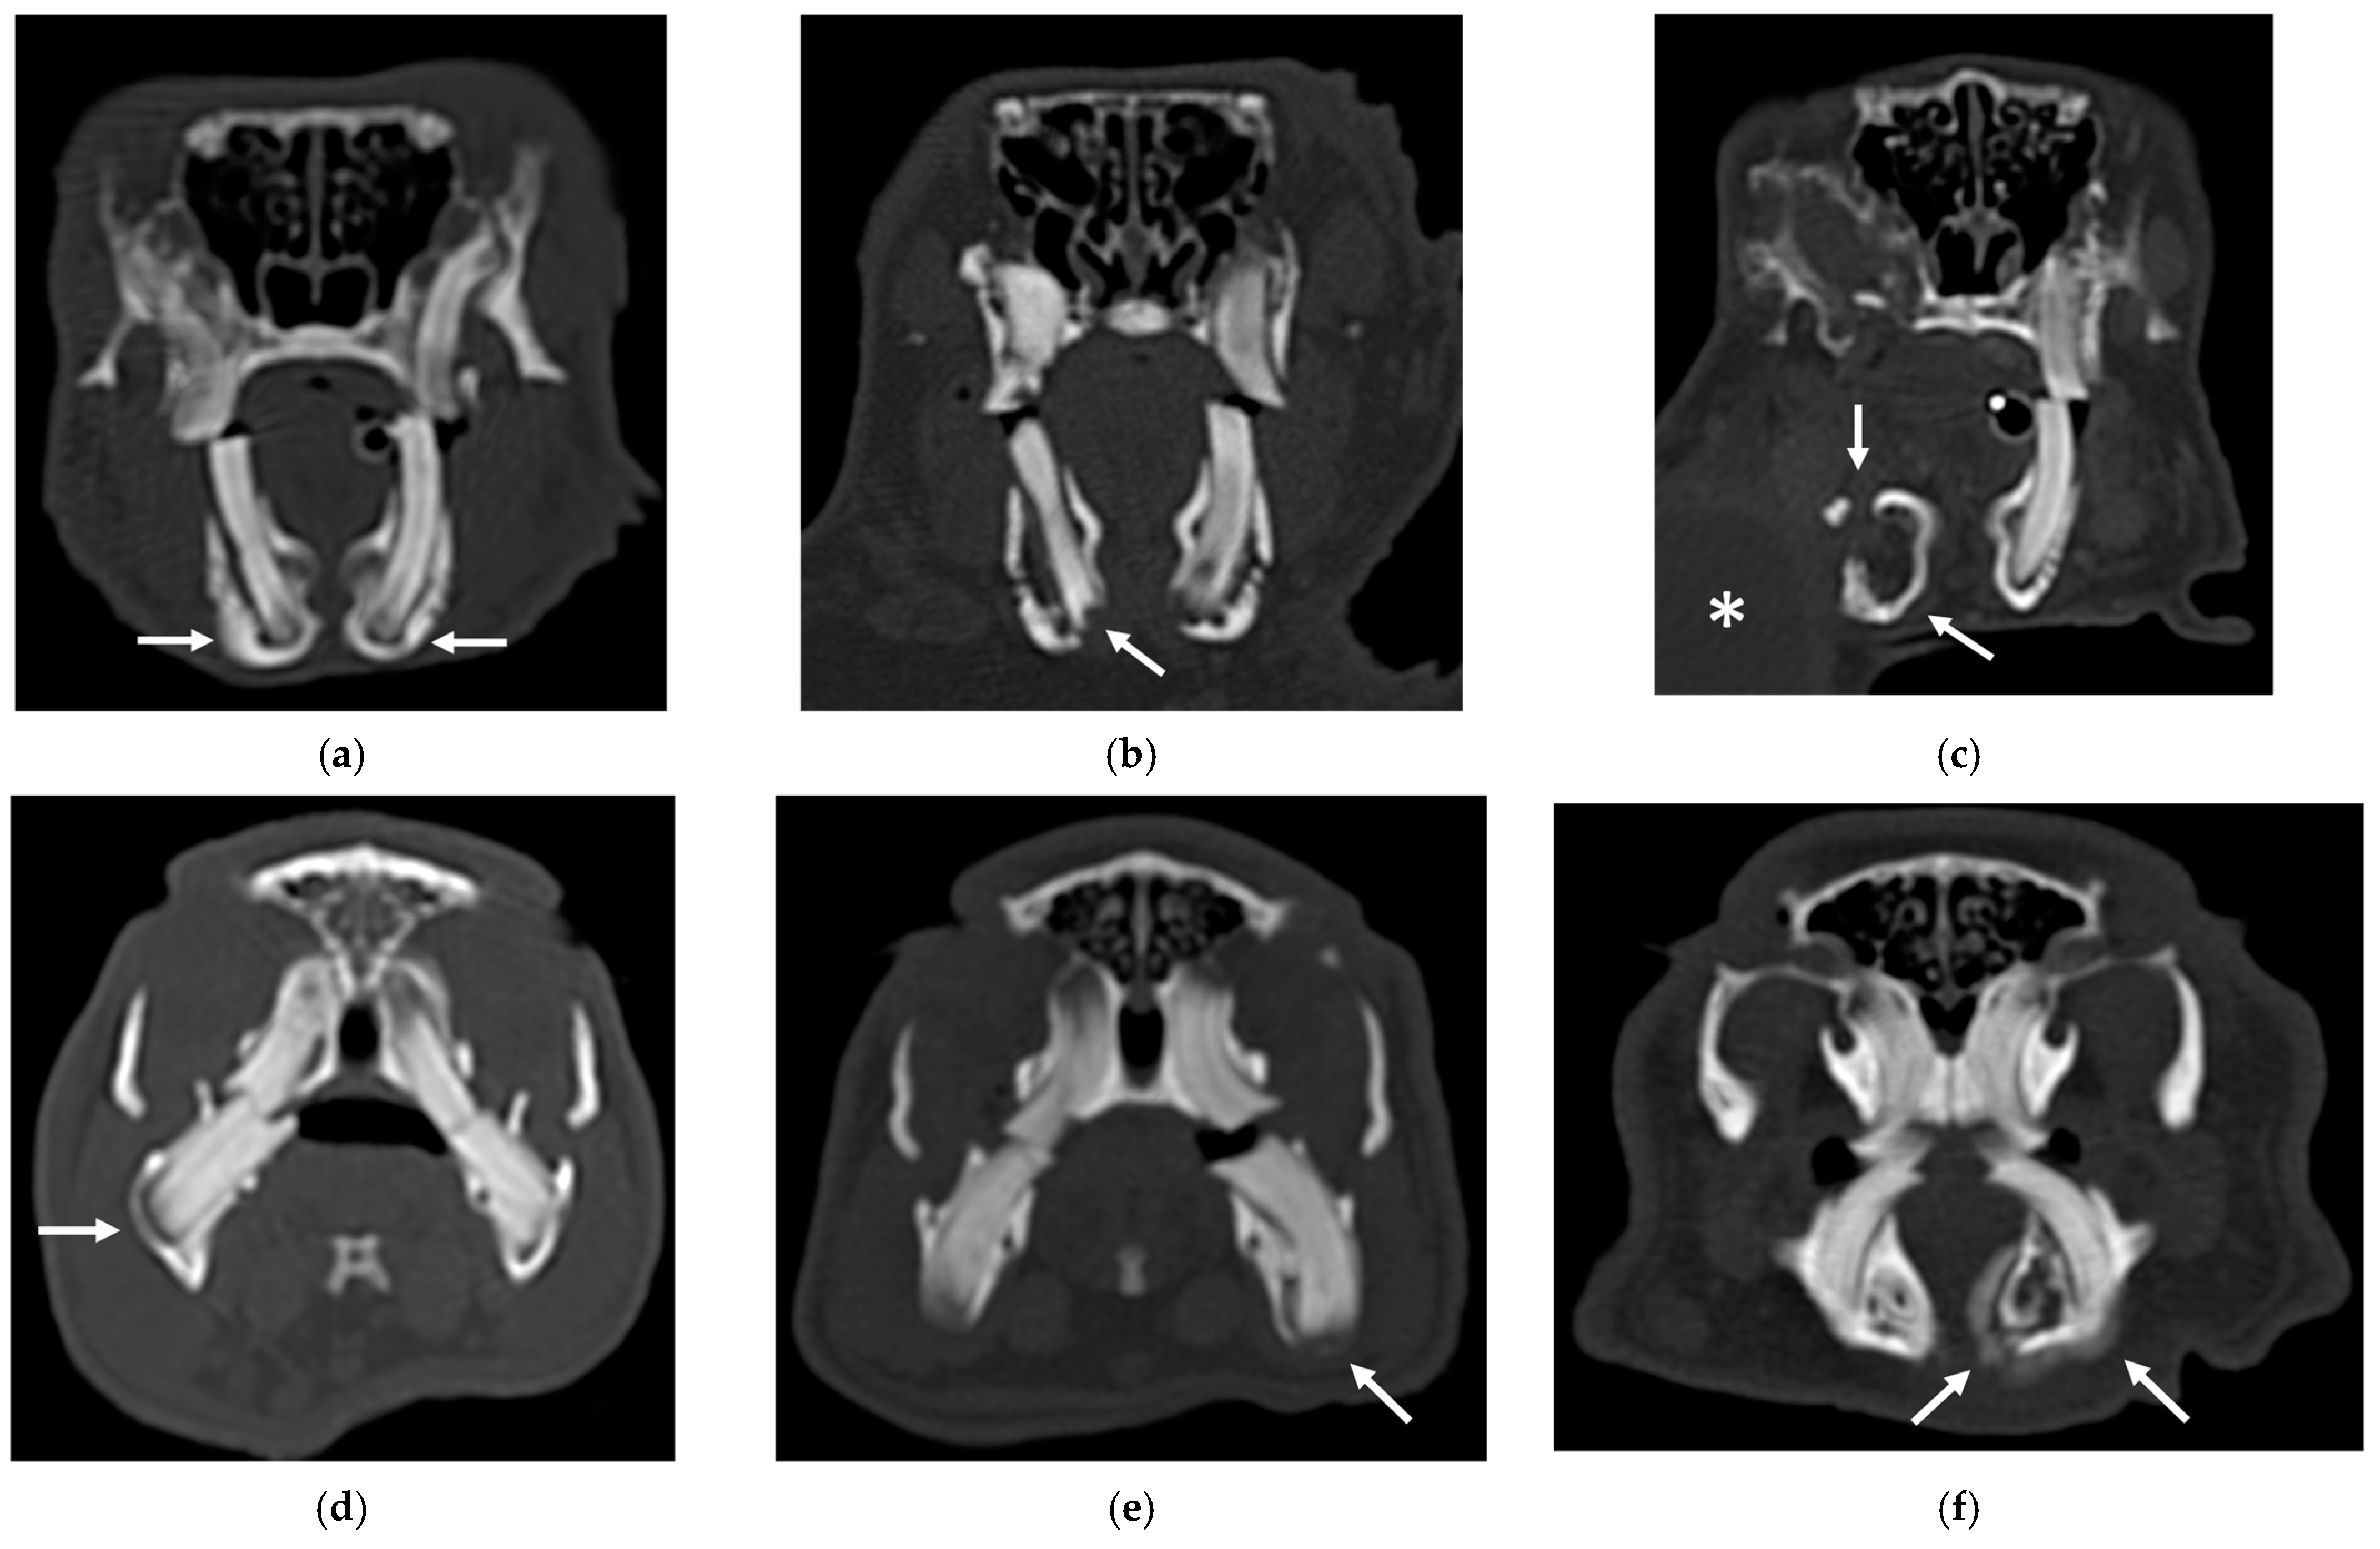

An example of the three categories of secondary bone lesions is shown for rabbits and guinea pigs in Figure 1.

Figure 1.

Transverse CT images of maxillary secondary bone lesions of three rabbits (a–c) and three guinea pigs (d–f) included in the study; bone algorithm. (a,d) Bulging around tooth without focal lysis (white arrow); (b,e) bulging around tooth with focal lysis (white arrow). Note the concomitant presence of nasolacrimalduct enlargement in image (b) (empty white arrows); (c,f) aggressive bone lesion associated with teeth (white arrow). Note the associated exophthalmos in the image (c) (white asterisk).